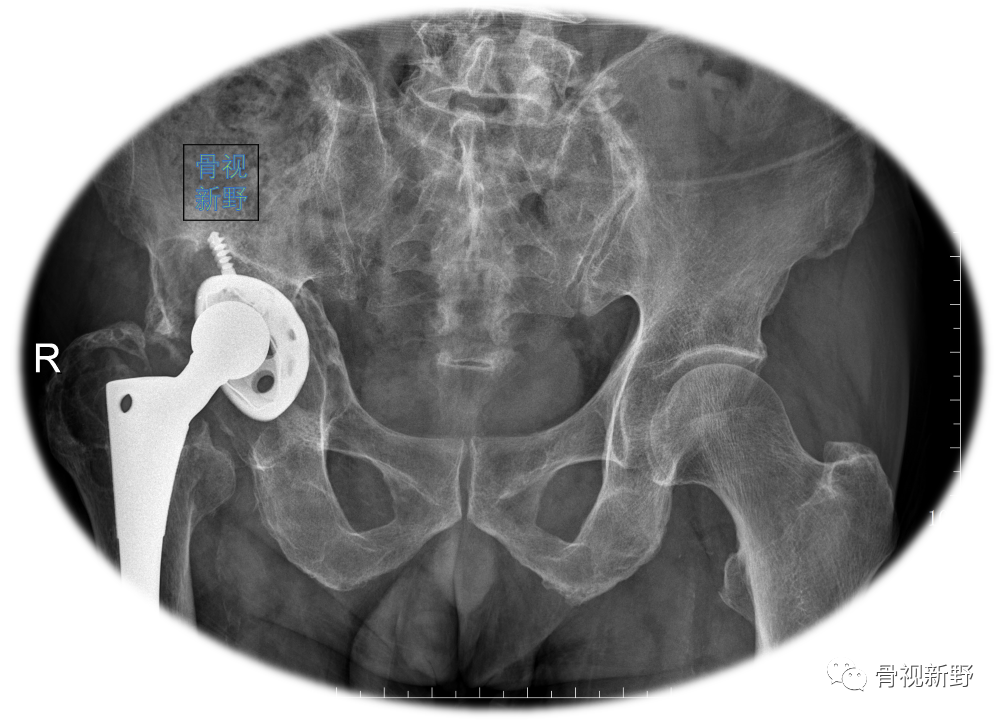

Case 1: Paprosky IIIb

男性,78岁。因右髋部骨折,于25年前行右髋THA。入院前半年开始出现右髋部疼痛、活动受限,加重1月。影像资料提示假体松动、移位;股骨侧及髋臼侧严重骨缺损(Paprosky IIIb )。

CT提示假体周围骨溶解、骨缺损严重

完善术前常规检查后,择期行翻修术:髋臼侧以cup-in-cup技术翻修;股骨侧以水泥柄翻修。

术后X光片